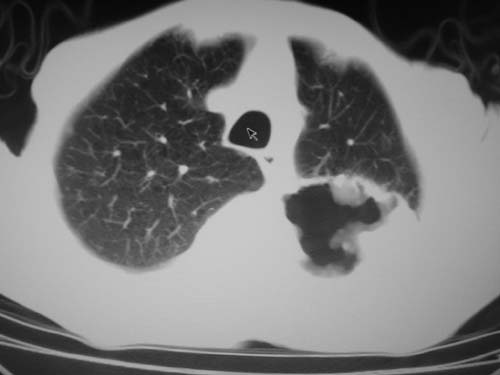

标题: CT19736:男,76岁,咳嗽,胸痛 [打印本页]

标题: CT19736:男,76岁,咳嗽,胸痛

支持左上肺周围型肺癌性并空洞形成伴胸椎转移。

左上沟癌空洞形成并胸椎转移。

考虑癌性空洞并胸椎转移。

空洞内壁有多发结节,支持癌性空洞。

左上肺癌性空洞伴胸椎转移。